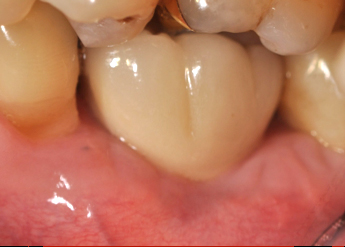

The crown and screw-retained custom abutment were removed, and a surgical cover screw was placed into the implant, thereby allowing spontaneous gingival augmentation in situ (Figure 33 and Figure 34). Note that the lingual aspect of the implant site was significantly more coronal than the labial aspect, which was positive because the defect would be limited to a facial–lingual defect. A fixed RBR bridge was cemented on the adjacent teeth and used as a tooth-supported transitional provisional restoration (Figure 35). A few weeks were allotted to let the soft tissue heal and migrate around the cover screw (Figure 36) to see if there would be complete coverage, thereby allowing a soft-tissue augmentation procedure to be performed with primary flap closure as in clinical scenario No. 2. The major obstacle in achieving a positive tissue response was that the implant depth was also deficient because the implant–abutment connection was at the level of the free gingival margin. It was decided that the best treatment option would be to remove the implant. A high-powered reverse-torque device (Fixture Remover Kit, NeoBiotech, www.neobiotechus.com) was used to remove the implant atraumatically (Figure 38 through Figure 41). The implant socket was allowed to heal for several months not unlike an extracted tooth (Figure 42). A new implant was placed in a better position from both a restorative and esthetic perspective (Figure 43), and after a few months of healing, a new crown was made (Figure 44). A satisfactory functional and esthetic result was achieved (Figure 45 and Figure 46) without employing pink porcelain.

Fig 44. A new metal-alloy abutment was fabricated for the narrow-diameter implant with a cement-retained metal-ceramic crown.

Fig 45. The definitive crown tooth No. 26 seated in place and provisionally cemented. The recession defect was eliminated with the removal and replacement of a new implant in the proper position.

Fig 46. The post-treatment radiograph showing a healthy stable implant and restoration.